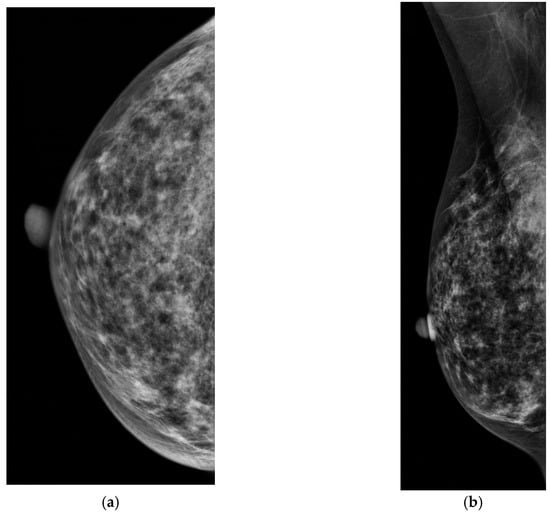

Dense breast tissue appears white on mammograms, as does breast cancer, which is why dense tissue can sometimes obscure a cancer. In contrast, dense tissue is echogenic on ultrasound, while breast cancer is hypoechoic. Ultrasound leverages the differences in tissue characteristics to improve cancer detection in women with dense breasts (Figure 2).

Figure 2.

A 43-year-old woman with extremely dense breast tissue. Dense tissue obscures a breast cancer that is easily visible with ultrasound imaging. (a,b) Craniocaudal (CC) and mediolateral oblique (MLO) digital mammography. (c) Handheld high-resolution ultrasound demonstrates a 1.2 cm irregular mass, denoted by calipers in the image, which was biopsied and proven to be invasive ductal carcinoma.